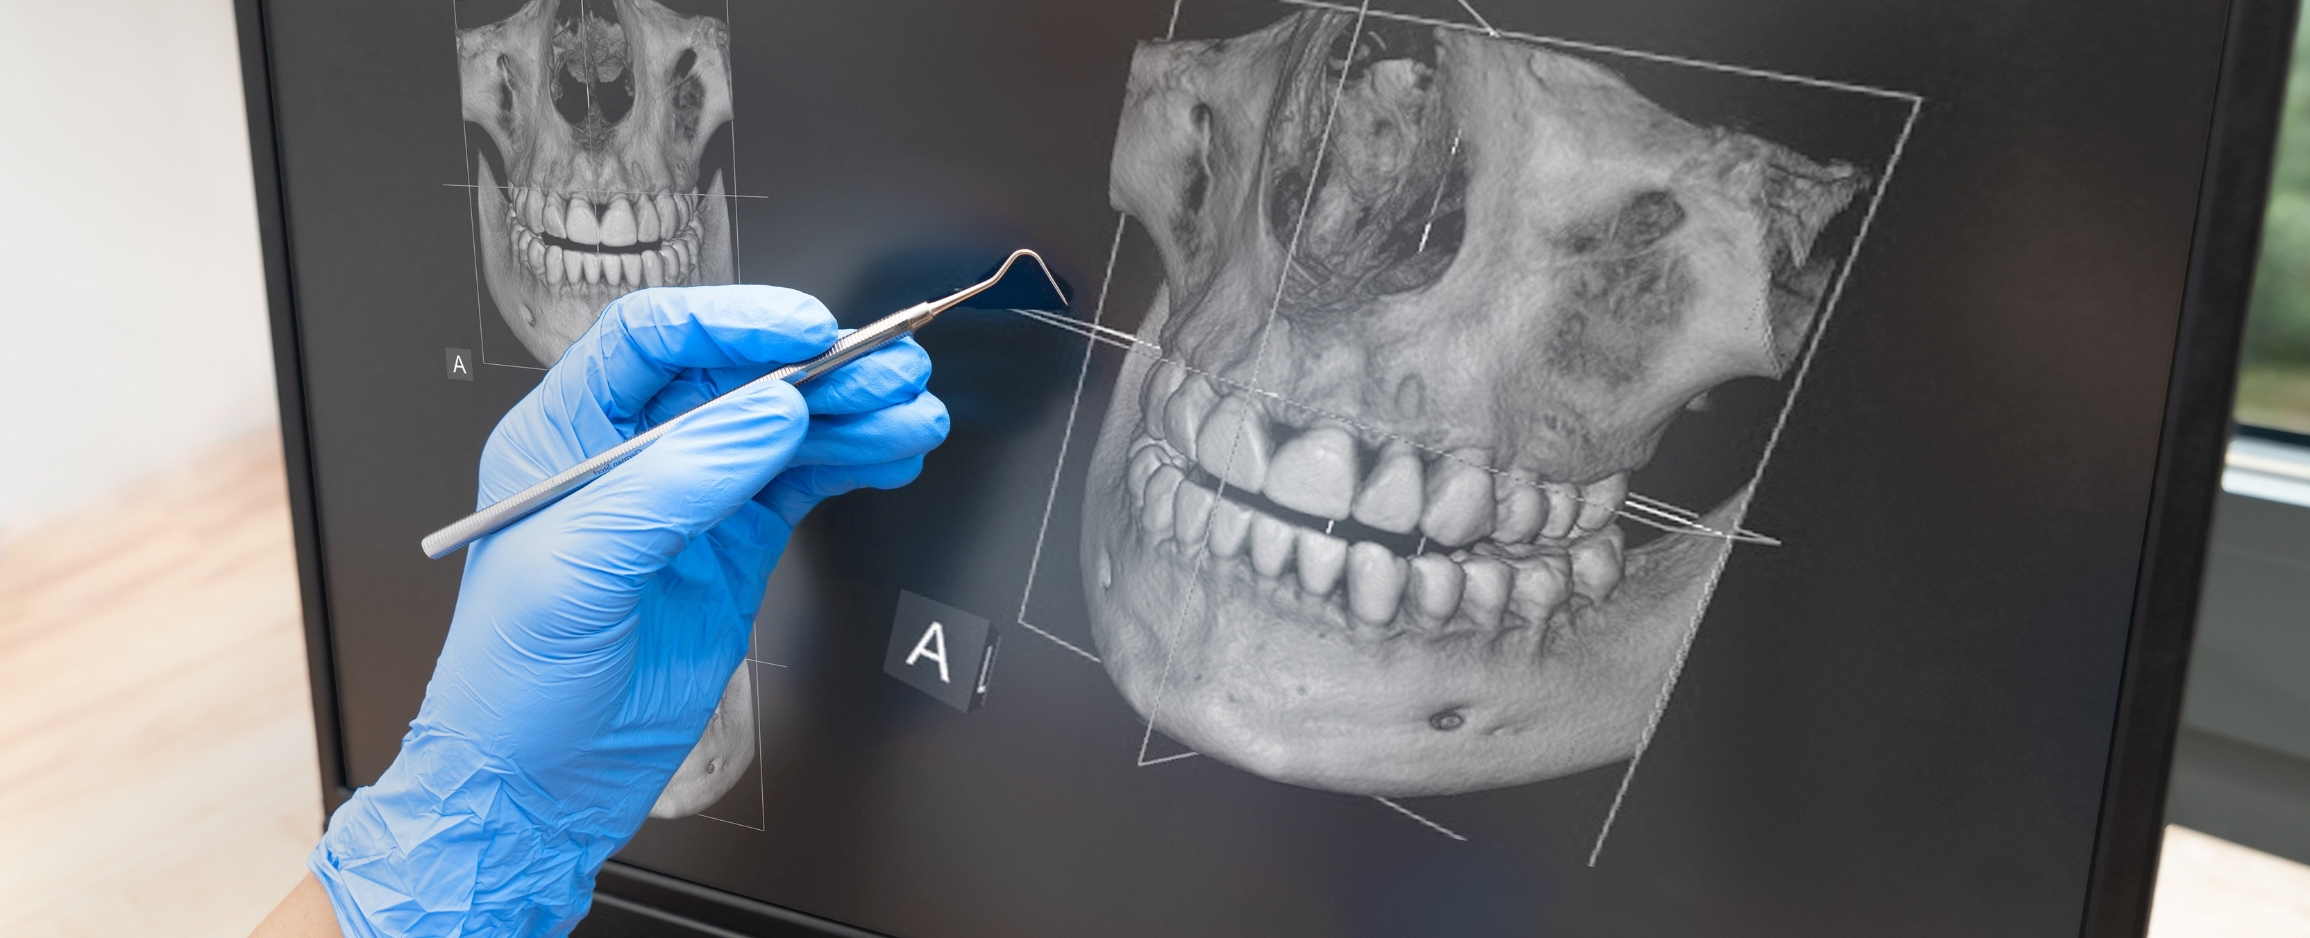

Dentistry is constantly evolving, and over the past 5 years, one of the biggest leaps in technology has come from imaging, which is used in the dental practice. At Buckden Dental Clinic, we have acquired a state-of-the-art 2D/CBCT Scanner developed by one of the leading dental imaging companies in the world, GENDEX, known for its reliable, innovative imaging equipment, and which offers a wide variety of solutions for both general dentists and specialists.

The company’s strong history in X-ray manufacturing, along with a deep dedication to delivering products that exceed the needs of dental professionals, has earned Gendex recognition as a global leader. The Gendex DP-700 gives clinicians dependable image capture of a wide variety of radiographs. These images are valuable for diagnosis and treatment planning of caries, root investigation, orthodontics, implants, and other surgical procedures, as well as patient education in both 2D panoramic and 3D CBCT scans.

With both Full arch and targeted sectional scanning, a CBCT scan can be achieved in the perfect location to suit the patient’s anatomy.

This gives both accuracy of imaging and dose reduction by only imaging and exposing what you want to see. The scanner offers an 8cm wide scan for full arch cases, allowing for a scan big enough to cover the full dental arch but small enough to minimise the reporting area to avoid areas such as the TMJ and spine. As well as the option to have a 4cm scan diameter to cover a section of the dentition of interest for smaller cases.